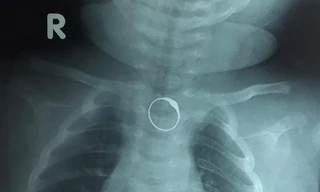

TPO - Bé gái 2 tháng tuổi được người nhà đeo cho chiếc nhẫn vàng ở ngón tay làm đồ trang sức. Tuy nhiên khi mút tay theo thói quen của trẻ mỗi khi đói, bé đã nuốt luôn chiếc nhẫn và phải nhập viện cấp cứu.